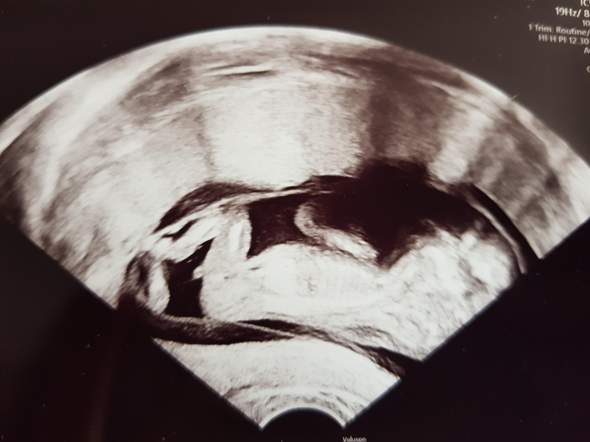

Geschlechtsbestimmung baby ultraschall. Ultraschall 32 SSW Hier sieht man, dass dieses Baby ein Junge ist Der kleine Penis ragt deutlich nach rechts ins Bild Wenn das Baby günstig liegt, kann man schon um die 14 SSW das Geschlecht erkennen Spätestens mit einem Ultraschallbild wie diesem ist dann aber klar, ob es ein Junge oder ein Mädchen wird ;. Geschlechtsorgane baby ultraschall Viele Eltern interessiert es brennend, das Geschlecht ihres Kindes schon vor der Geburt zu erfahren Die beste Zeit ist dafür bei Ihrem zweiten regulären Ultraschall, der ungefähr in Schwangerschaftswoche anstehtDann ist es ziemlich einfach, das Geschlecht zu bestimmen, wenn sich Ihr Baby dem Gynäkologen/ der Gynäko im Ultraschall gut präsentiert Aus dieser entwickeln sich die Geschlechtsorgane. Cancel Unsubscribe Working Subscribe Subscribed Unsubscribe 52K Loading.

Auch für Dein Baby ist diese Schlafposition gut Durch die seitliche Lage wird die Plazenta optimal mit Blut und Nährstoffen versorgt und damit auch Dein Baby Was ist in der 12 SSW auf dem Ultraschall zu erkennen?. Ultraschall 32 SSW Hier sieht man, dass dieses Baby ein Junge ist Der kleine Penis ragt deutlich nach rechts ins Bild Wenn das Baby günstig liegt, kann man schon um die 14 SSW das Geschlecht erkennen Spätestens mit einem Ultraschallbild wie diesem ist dann aber klar, ob es ein Junge oder ein Mädchen wird ;. Mein erstes Baby, Ultraschall in der 19 SSW und es wird ein Junge.